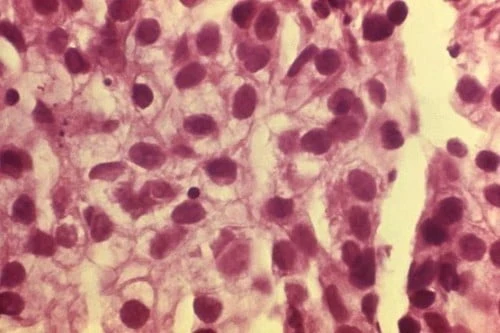

2. John Hopkins sugiere cambios en la dieta y el estilo de vida para eliminar el cáncer

Estado: Falso

Un correo electrónico reenviado es viral en Internet que sugiere que los cambios en el estilo de vida y los hábitos alimentarios no solo previenen el cáncer sino que también lo eliminan. De hecho, el contenido del correo electrónico comienza con los efectos negativos de la quimioterapia. Los legos asumen que traer mejoras en la dieta y el estilo de vida, como comer menos proteínas, ácidos o carbohidratos, y más pescado, evitar el plástico y el microondas, etc., funciona mejor que la quimioterapia, lo cual va en contra de la ciencia médica actual. Este artículo engañoso, de hecho, ha sido desaprobado por John Hopkins.

5. El limón, los espárragos, la jaca y la graviola curan el cáncer

Estado: Falso

Las constantes acciones en Facebook no hacen más que generar falsas esperanzas en la mente de las personas. Aunque se ha descubierto que estas frutas y verduras tienen potencial para combatir el cáncer, no se ha probado nada más. Quizás la más popular de estas frutas supuestamente anticancerígenas es la graviola o fruta de guanábana con propiedades citotóxicas. Aunque los científicos creen que sus propiedades permitirán que se use algún día para un ataque seguro contra el cáncer, aún no se han realizado pruebas en el cuerpo humano. De hecho, no se recomienda usar su jugo solo para revertir el cáncer o matar células cancerosas.